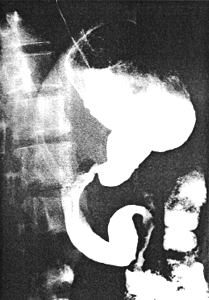

Case 39.2 D.P., 23 year old male, swallowed half a tumblerful of hydrochloric acid in an attempted suicide. After some hours he was admitted to a peripheral hospital where gastric lavage with dilute alkali was performed. Dysphagia and continuous vomiting necessitated oesophagoscopy after 10 days. This showed mucosal erosions and moderate oesophageal stenosis at 33cm. Upper gastrointestinal barium examination revealed a constant narrowing of the distal third of the stomach with absent cyclical contraction and relaxation of the pyloric sphincteric cylinder (Fig 39.2). This was associated with a patent pylorus and rapid emptying of fluid barium. The entire duodenum showed loss of mucosal pattern with rigid walls; immediately beyond the duodeno-jejunal flexure a 3.0cm long stenotic area was evident.

| Fig. 39.2. Case D.P. Constant narrowing distal third of stomach. Pyloric aperture patent. Absent cyclical activity of pyloric sphincteric cylinder. Duodenal walls rigid. Stenosis proximal jejunum |